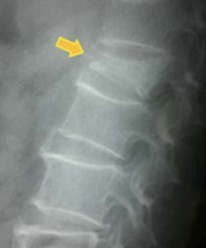

• X線(レントゲン)検査:背骨の形や並びを確認し、骨折の有無やつぶれの程度、過去の骨折の痕跡がないかを調べる基本的な検査です。骨の変形や椎体のつぶれ具合を把握するために使われます。